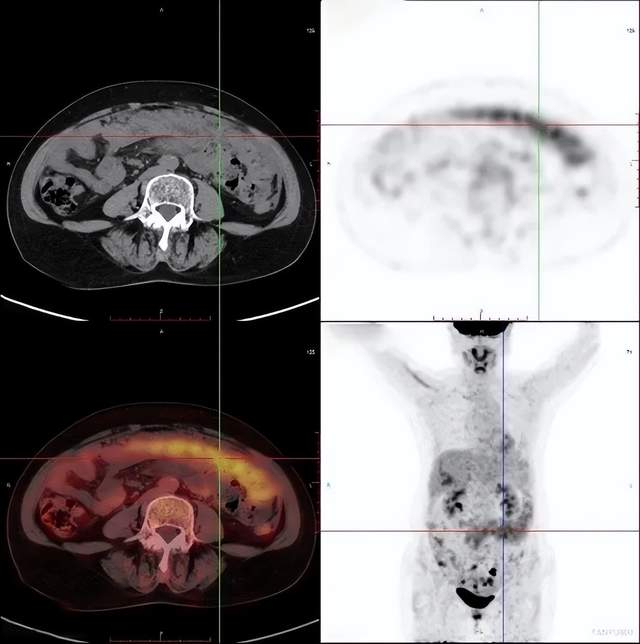

PET/CT检查卵巢癌

女性,60岁

相关病史:宫颈高级别鳞状上皮内病变(HSIL)锥切术后4月;否认结核及其他慢性病史。无其他临床症状。已绝经,无外伤史。2021-3-21日,患者因检查发现CA125渐进升高(250U/mL)后,在平安健康(检测)中心接受PET/CT检查。

PET/CT影像学表现

结论: 盆腔双附件区结节灶(左侧著)、右侧膈前上、肝脏包膜及腹盆腔多发结节灶、腹膜后多发淋巴结FDG代谢增高,考虑:卵巢癌(源于左侧卵巢可能性大)并上述部位多发转移瘤

PET/CT结论与病理结果对比

PET/CT结论:

考虑:卵巢癌(源于左侧卵巢可能性大)

手术病理结果:

卵巢癌

对比结论:

PET-CT实现肿瘤的精准定位及确诊。